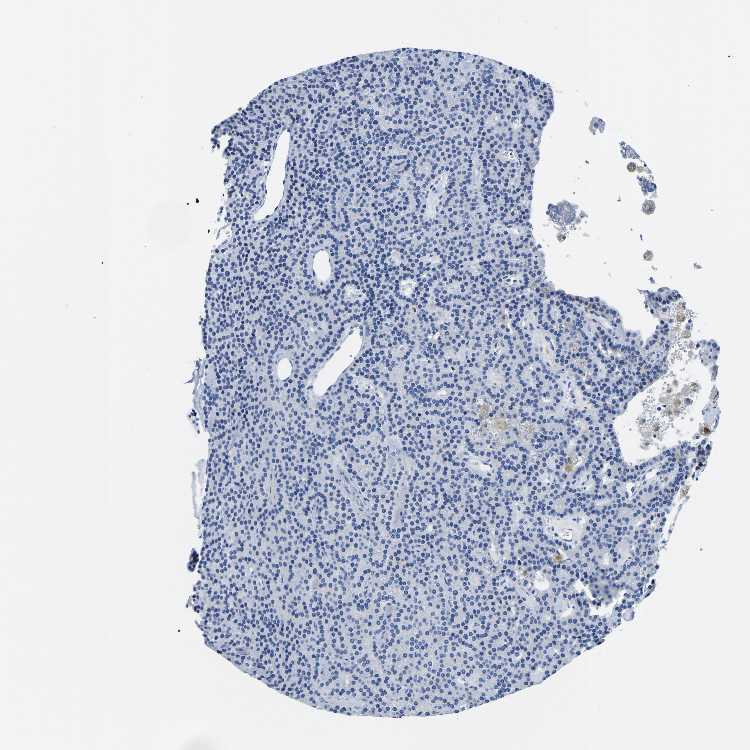

TISSUE PRIMARY DATA PARATHYROID GLAND Show tissue menu

PARATHYROID GLAND - Antibody stainingi

Antibody staining in the annotated cell types in the current human tissue is reported as not detected, low, medium, or high, based on conventional immunohistochemistry profiling in selected tissues. This score is based on the combination of the staining intensity and fraction of stained cells.

Each image is clickable and will lead to virtual microscopy that enables deeper exploration of all samples and also displays staining intensity scores, fraction scores and subcellular localization as well as patient and tissue information for each sample.

Antibody CAB016531

Glandular cells Not detected